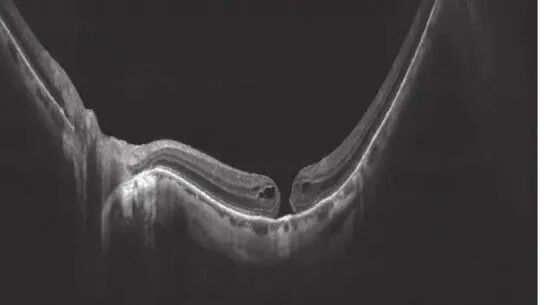

视网膜变性、裂孔及视网膜脱离